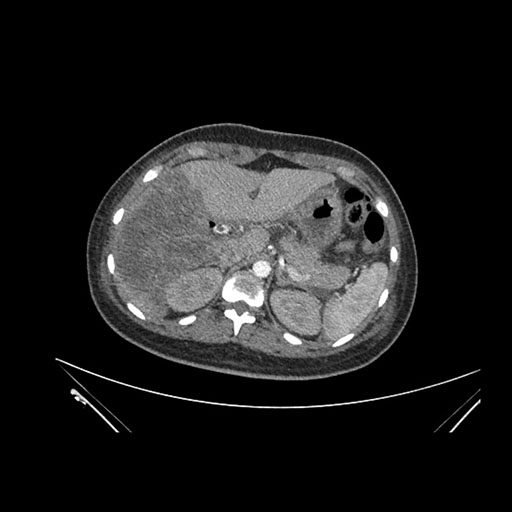

Imaging Analysis

Look through the patient's CT scan to identify any areas of concern for the necessary procedure.

Axial Venous

Based on initial findings, which issue(s) would you be most concerned about?